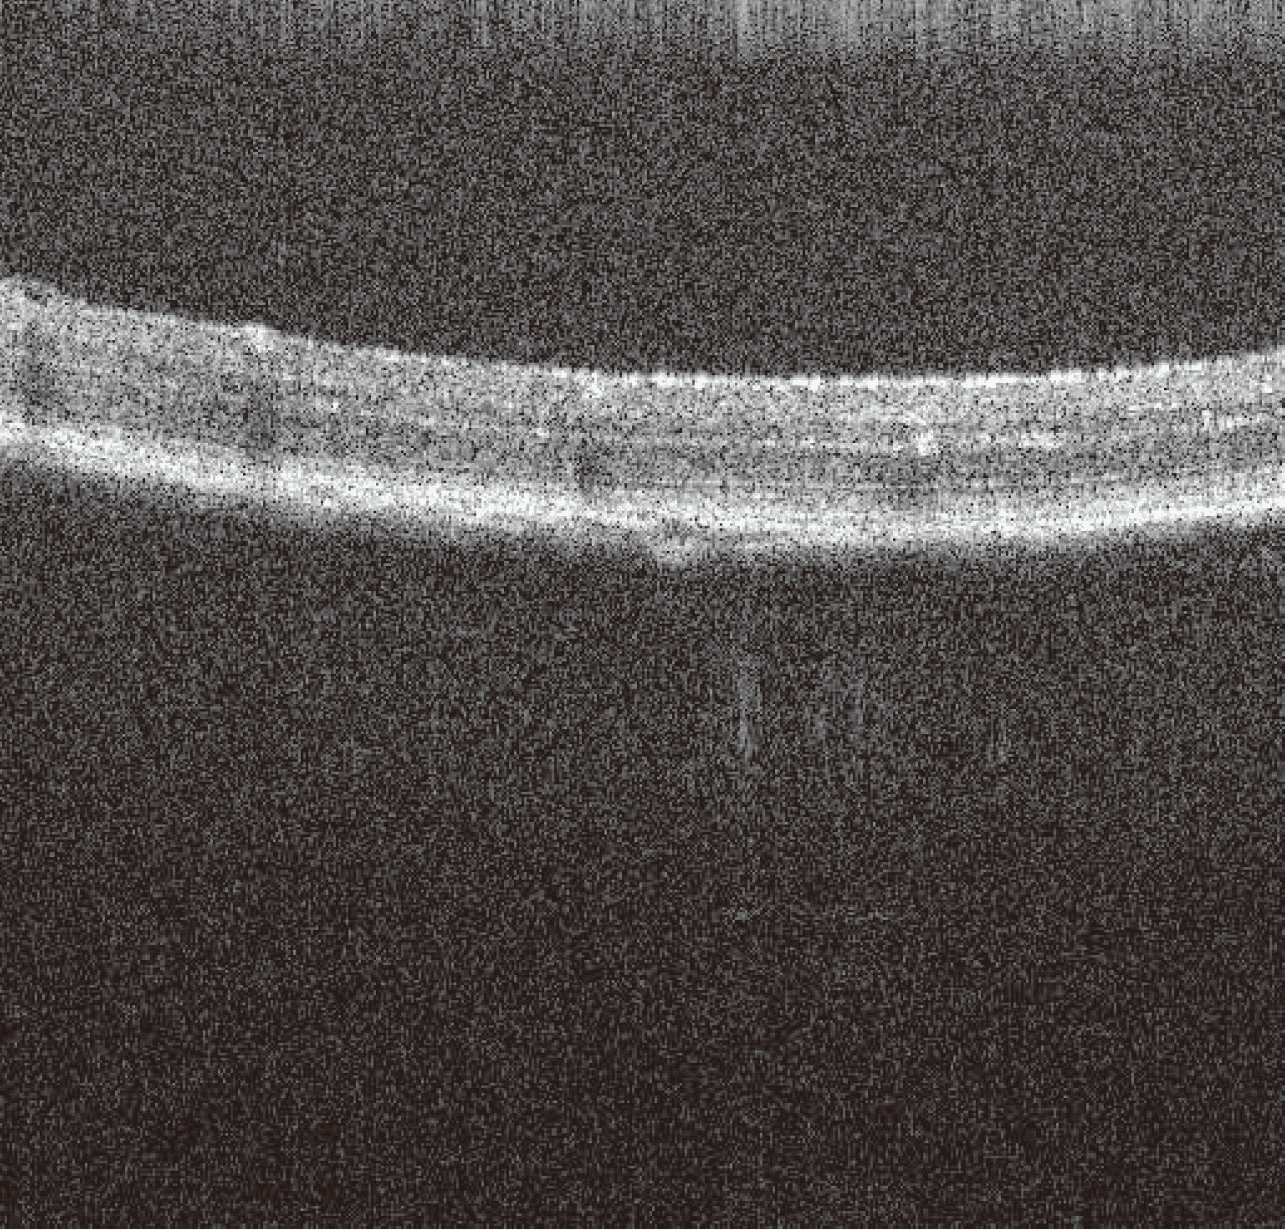

쥐 망막

토끼 망막

토끼 시신경

돼지 각막

OcuScience iVivo VET-OCT 시리즈는 이러한 연구 목적에 특화되어 설계되었으며, 축 방향 분해능을 3μm까지 향상시켜 더욱 정밀한 영상 구현이 가능하고, 최대 80kHz의 스캔 속도를 제공합니다.